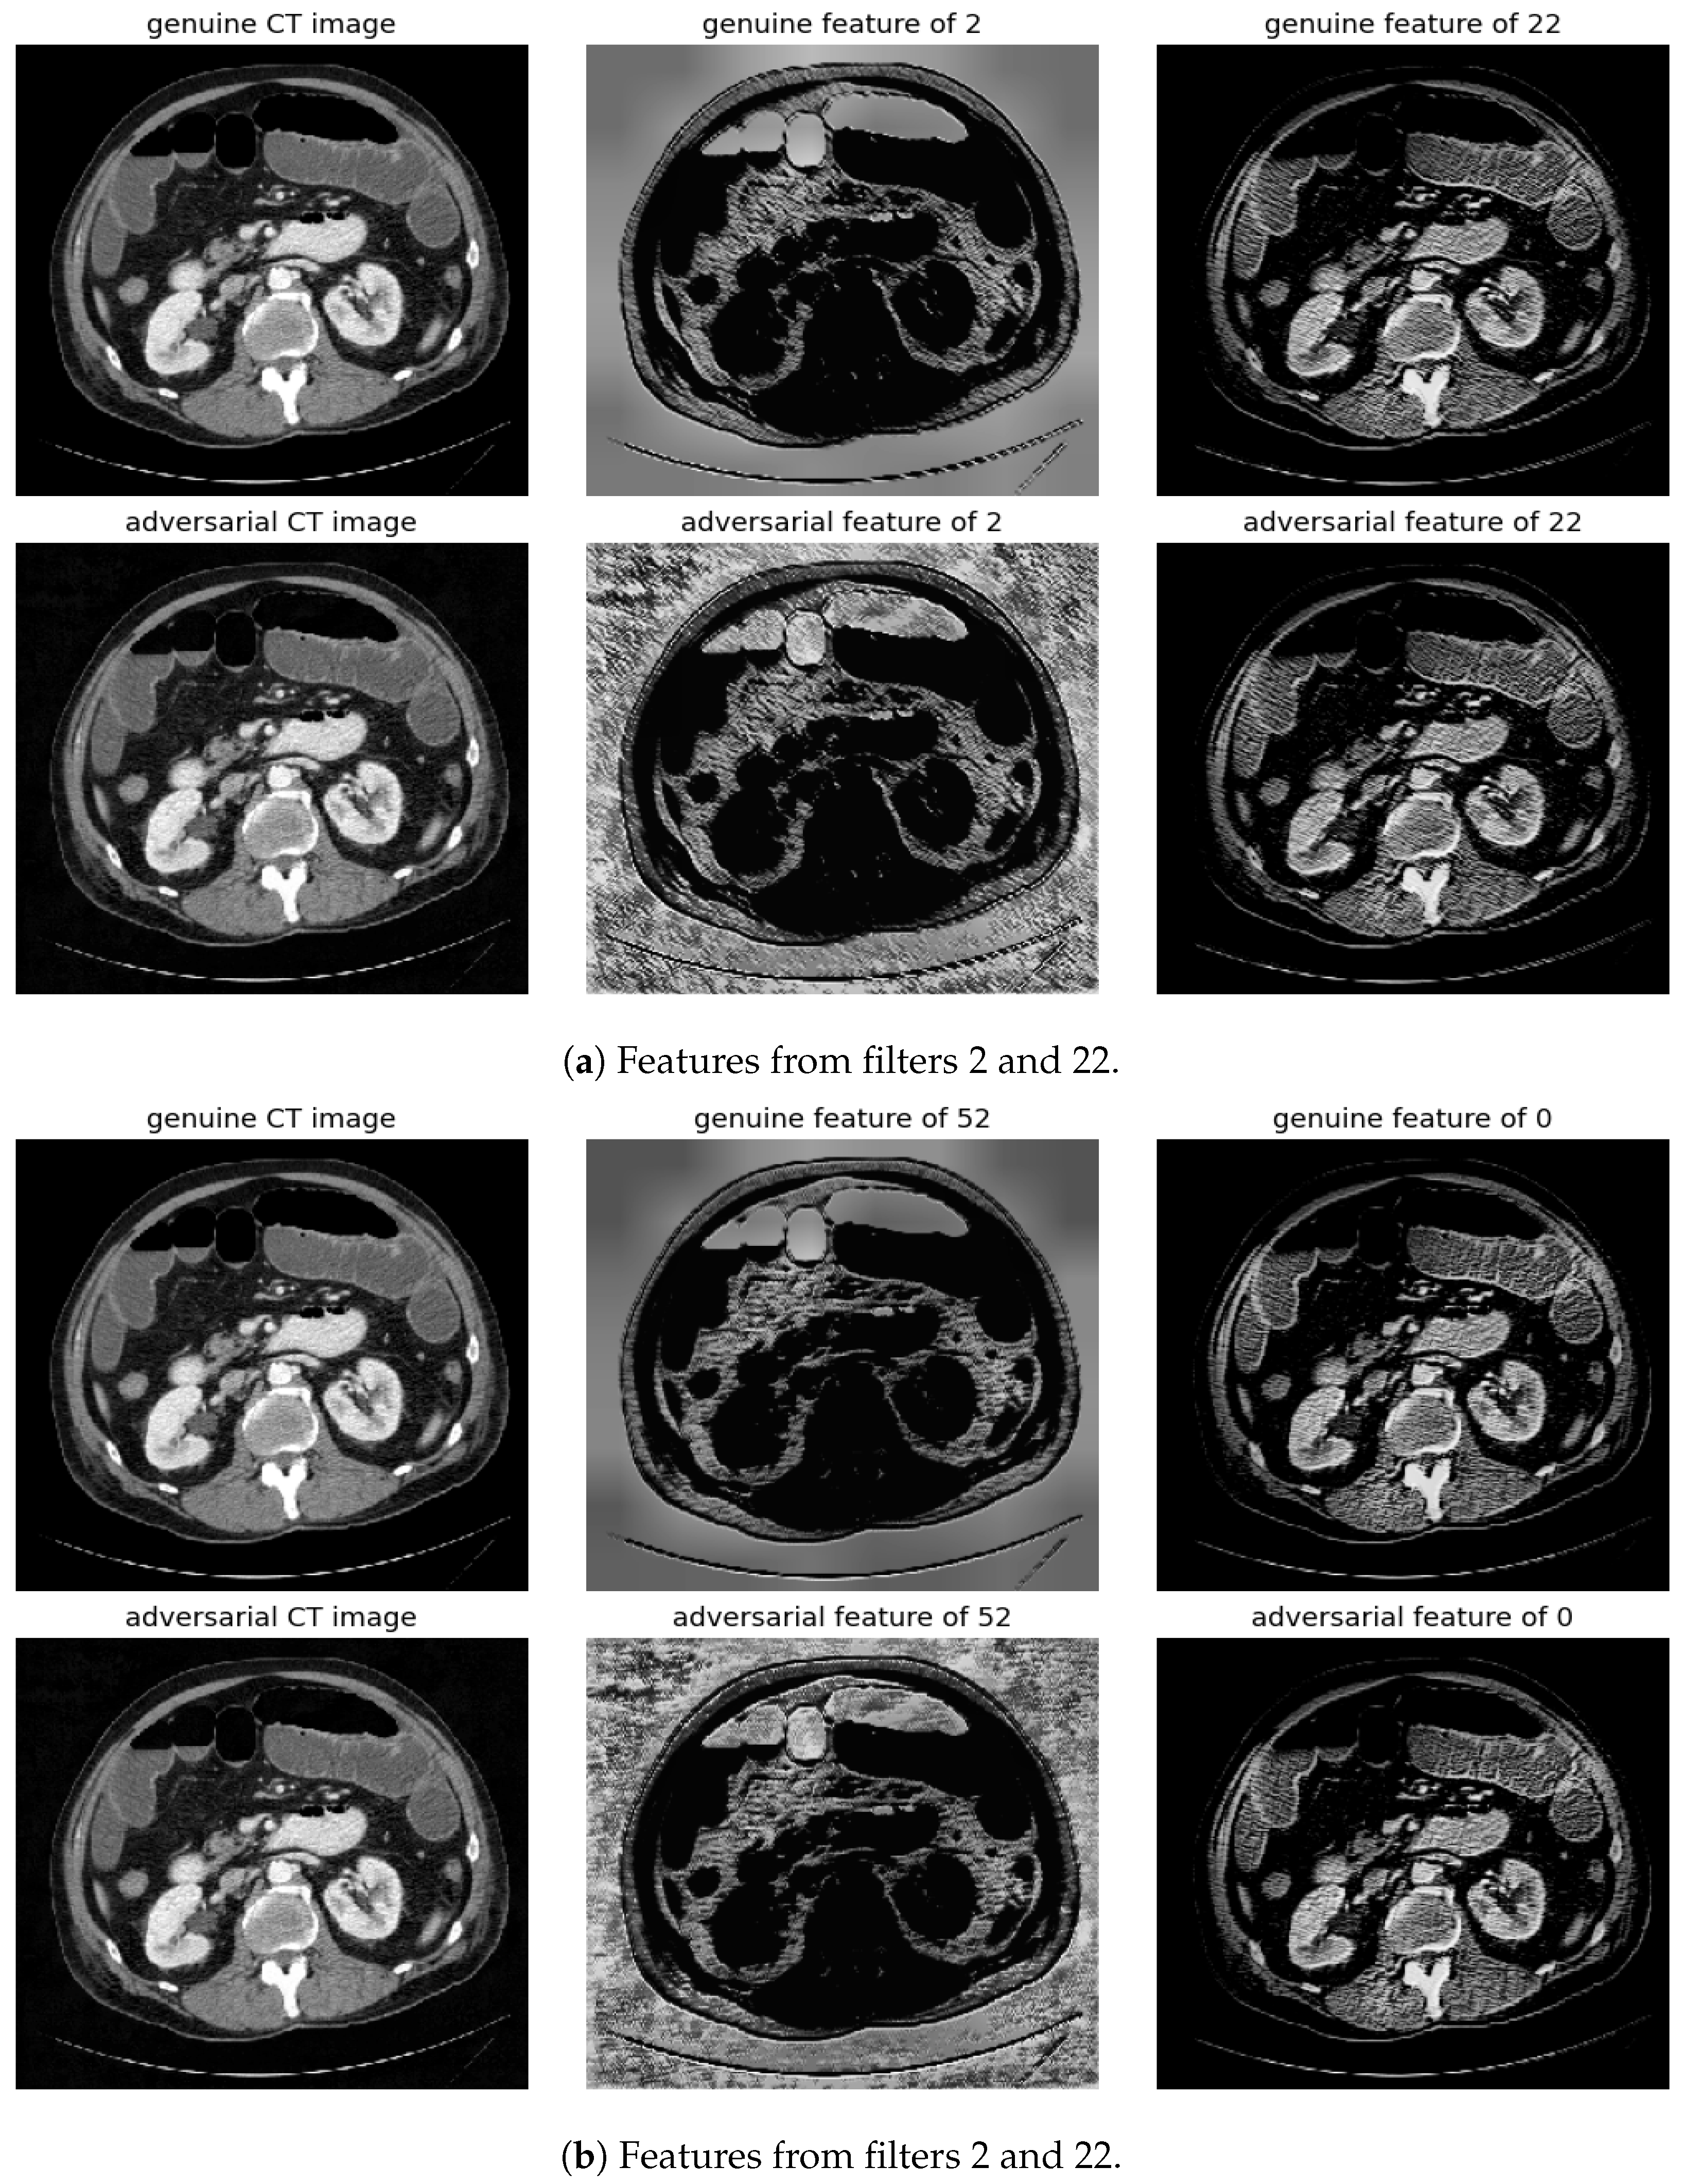

The significance of features associated with the most and least distinctive filters, specifically filter number 2 and filter number 22, is additionally examined. This analysis is conducted across FGSM, BIM, and SMIA for scenarios involving an epsilon of 0.01 and five iterations, excluding FGSM, as illustrated in Figure 7. The evaluation of feature importance is based on the mean decrease in impurity, a method used to assess how dependent variables impact prediction error in random forests [20]. The top 1% of features are presented according to their importance values. As indicated in the figure, the most distinctive feature predominantly concentrates on the background rather than the body, thus enabling easier distinction of adversarial samples from genuine ones. In contrast, the least distinctive feature primarily focuses on the structures surrounding the vertebrae, which may complicate the detection of attacks.

Randomly selected genuine CT samples, alongside their adversarial versions, are displayed in Figure 9, Figure 10 and Figure 11. The adversarial samples were generated using FGSM, BIM, and SMIA attack methods, each with an epsilon of 0.01. While BIM and SMIA used 5 iterations, FGSM did not. These samples represent the most challenging scenarios for human visual detection. Despite the modest epsilon value, as indicated in Table 3, the adversarial attacks have a subtle but pronounced effect. Such slight modifications can lead to major diagnostic inaccuracies potentially impacting patient care.

To address this, histogram equalization as feature post-processing is applied. The visual representations underscore that while genuine and adversarial samples might appear similar to the naked eye, post-processing brings forth distinct feature differences when employing the most sensitive filters from 2 and 52. Perturbations, especially noticeable in the background of the adversarial samples, are frequently highlighted by these filters. Conversely, features processed with filters from 22 and 0, deemed less sensitive in prior analyses, fail to offer a stark visual contrast.

Figure 9. Visualization under FGSM Attack: Comparison of features from the first layer between genuine and adversarial samples for the most sensitive (filters 2 and 52) and least sensitive (filters 22 and 0) filters.

Figure 10. Visualization under BIM Attack: Comparisons of features from the first layer between genuine and adversarial samples for the most sensitive (filters 2 and 52) and least sensitive (filters 22 and 0) filters.